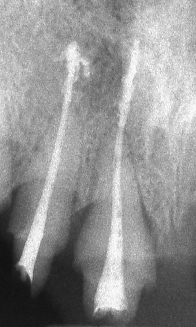

Запълване с препресване

Ендодонтия